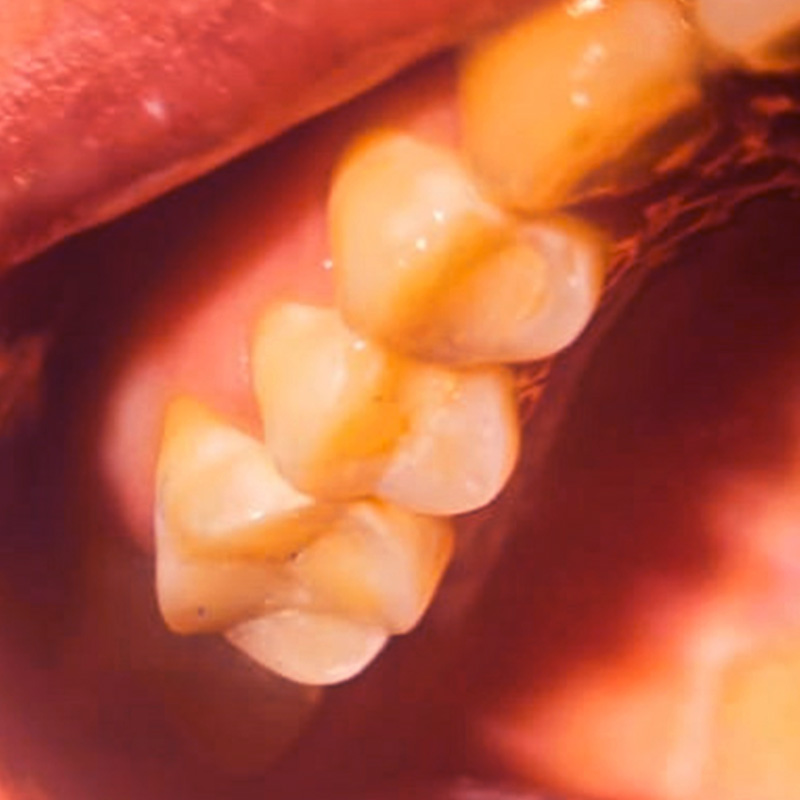

До и после лечения

В нашу клинику обратилась пациентка с жалобами на выпадение пломбы из 37 зуба. Её беспокоили кратковременные болевые ощущения от холодного и при попадании пищи. Во время осмотра был поставлен диагноз: хронический глубокий кариес 37 зуба (медиально-окклюзионно-дистально).